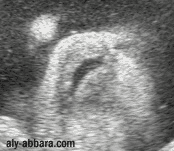

Ftus à 37 semaines d'aménorrhée

La bouche vue de face avec les lèvres en mouvements de succion.